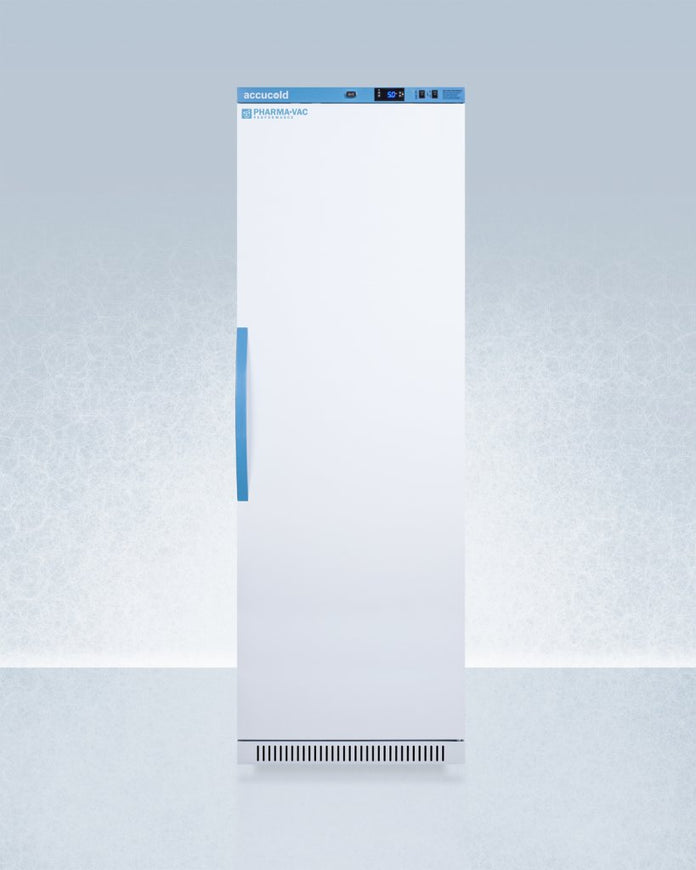

Accucold - ARS15PV-CRT - 15 Cu. Ft. Upright Controlled Room Temperature Cabinet

Controlled Room Temperature (CRT) cabinets are designed and purpose-built for ambient medication and vaccine storage in pharmacy and patient care areas

Door:White

Cabinet:White